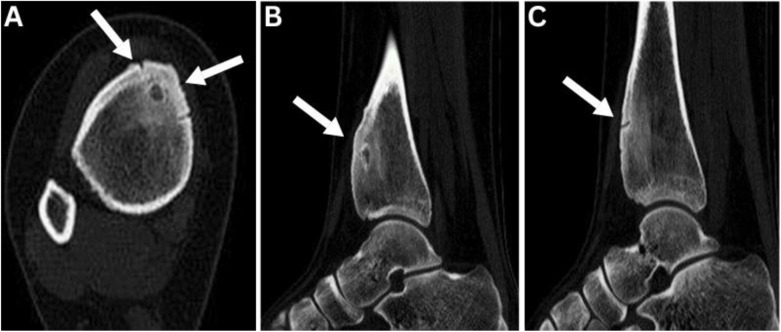

Osteoid osteomas (OO) are benign neoplasms commonly present during the second and third decade of life, showing a male predominance with classical nocturnal bone pain dramatically responding to nonsteroidal anti-inflammatory drugs. We report a 22-year-old female patient who presented at a teaching hospital, Baghdad, Iraq, in 2023. She presented with right leg bone pain that was exacerbated during menstruation, a presentation that had never been reported in the literature before. The pain intensity increased and interfered with her daily activity. A computed tomography scan showed OO signs and surgical excision and histopathology confirmed OO. The patient's pain reduced to 0 on the visual analog scale. She has no recurrence signs 2 years after the surgery. This novel OO presentation may increase physician awareness of atypical presentation. A careful evaluation of a challenging presentation added to an imaging study may reveal the underlying cause and exclude other diagnostic dilemmas.